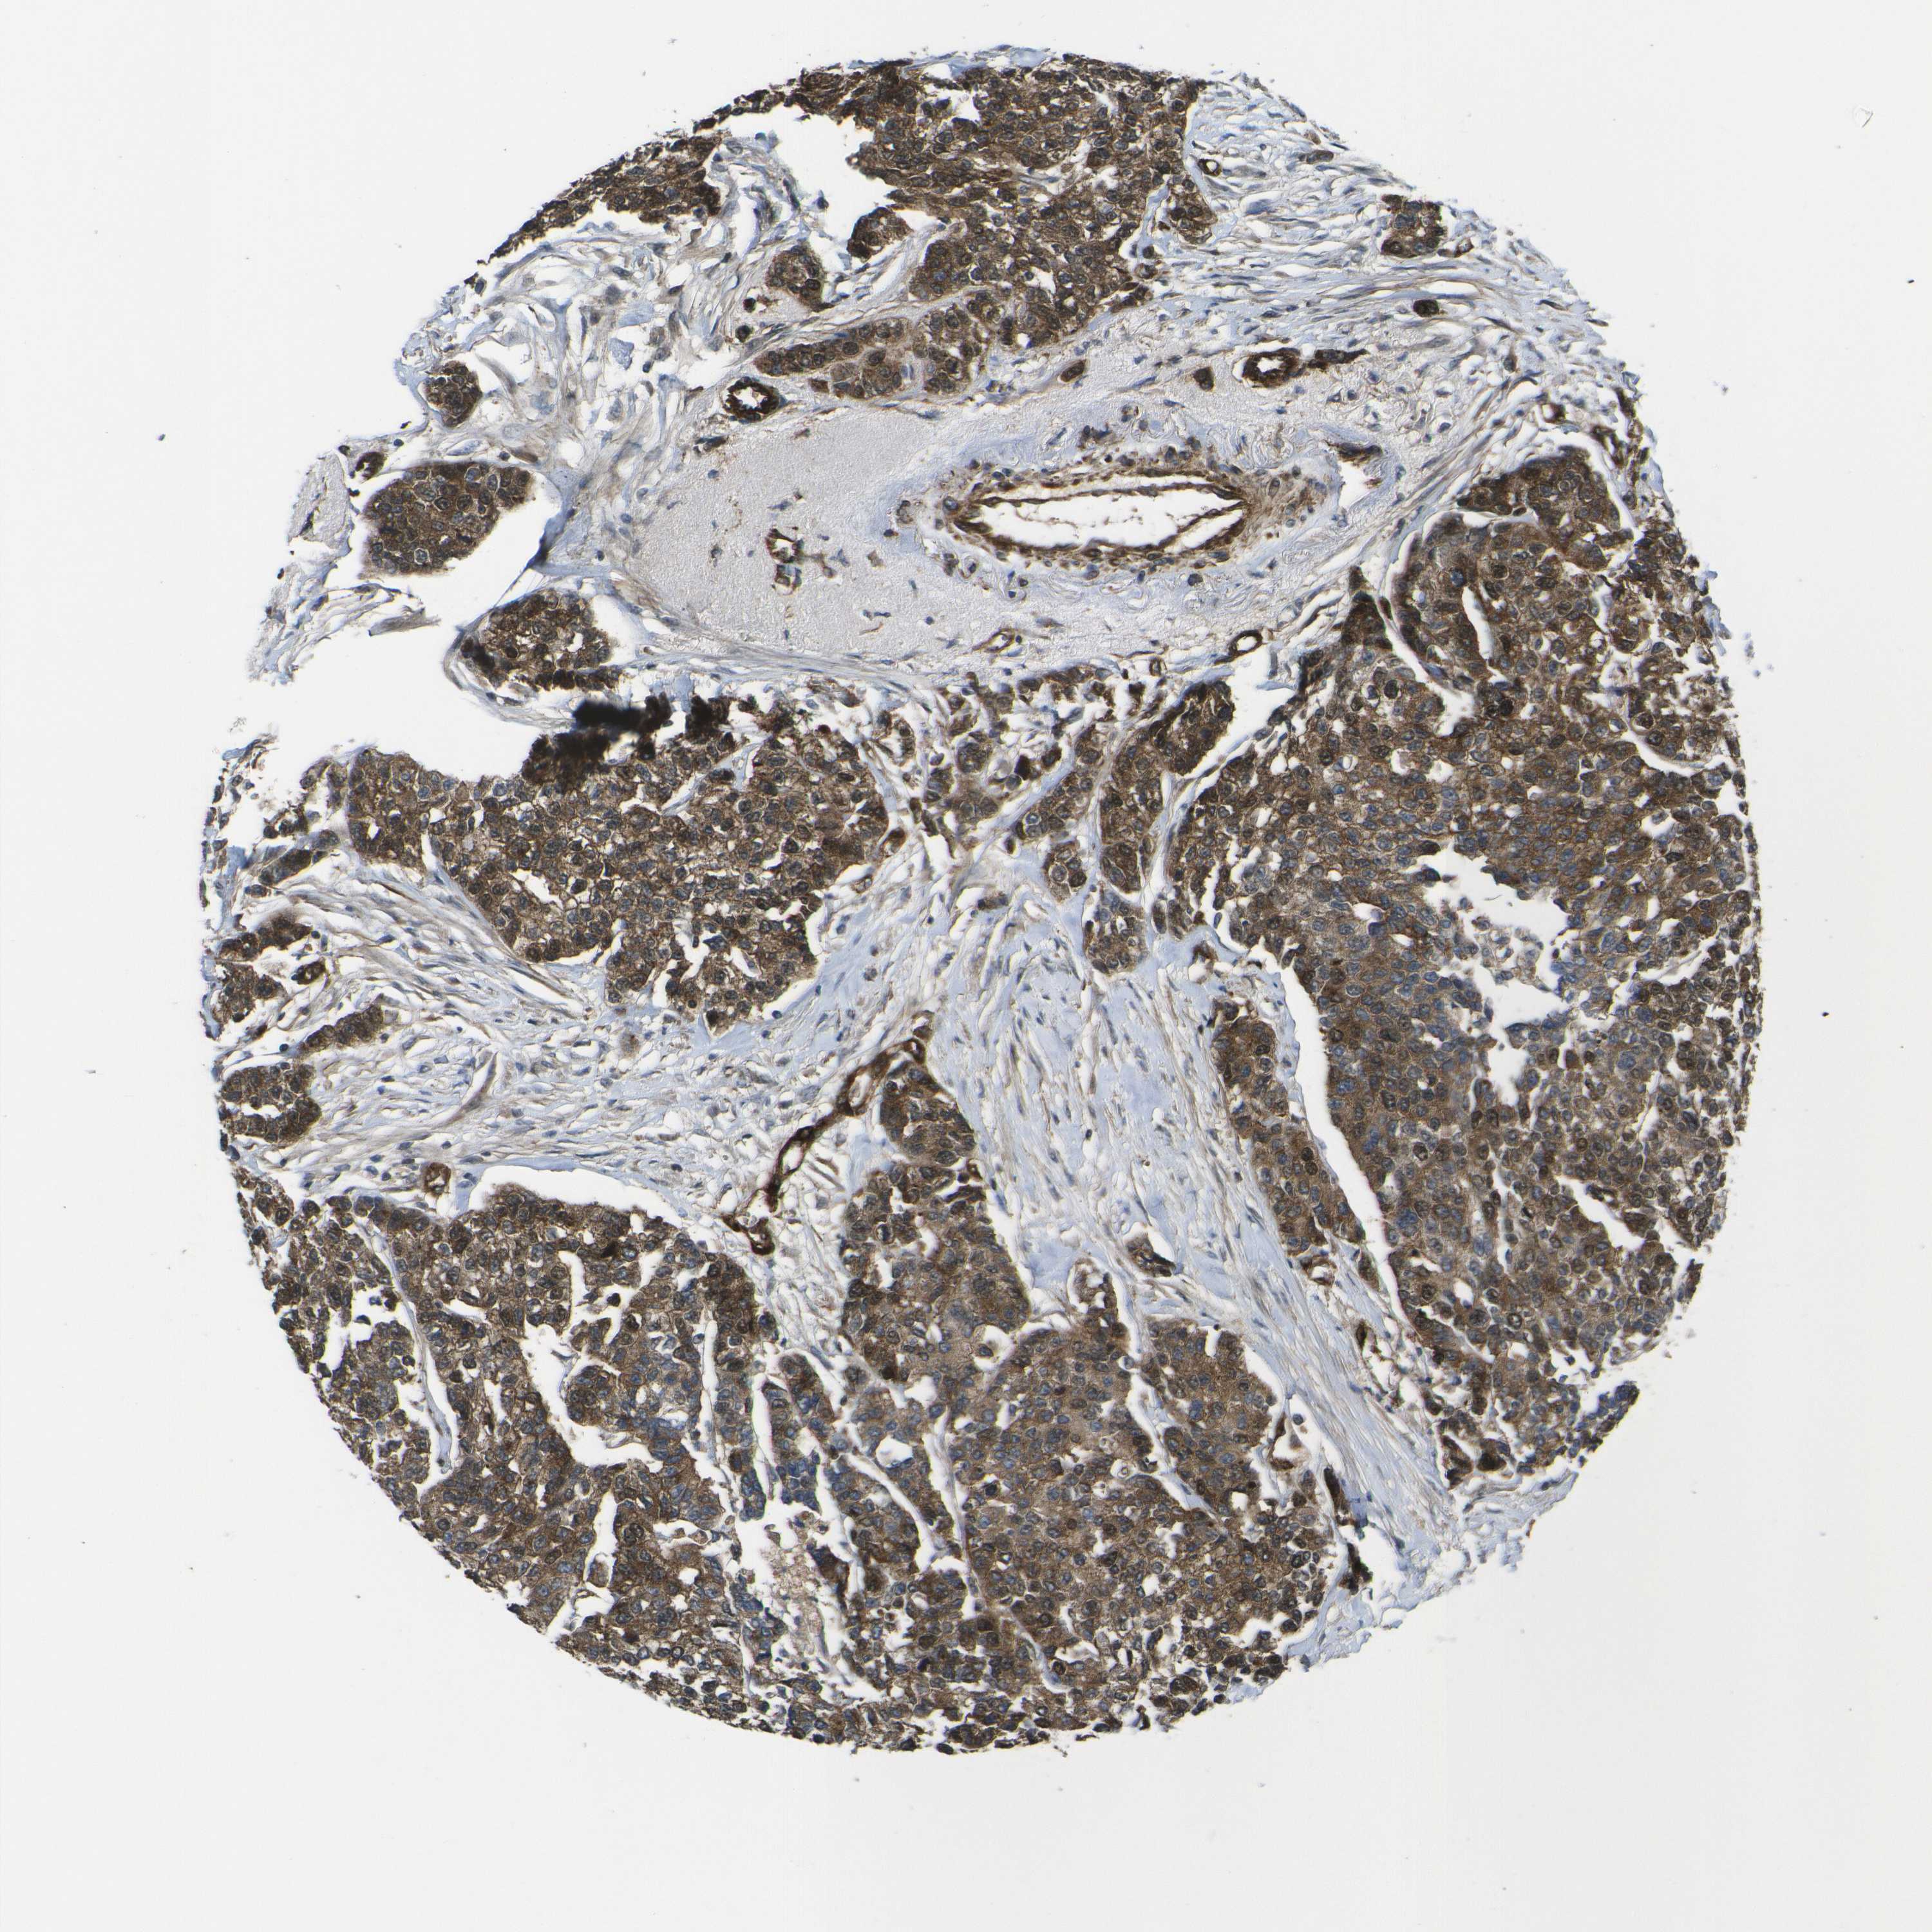

BRCA TCGA BRCA VALIDATION PROTEIN EXPRESSION

ANTIBODIES

AND

VALIDATION